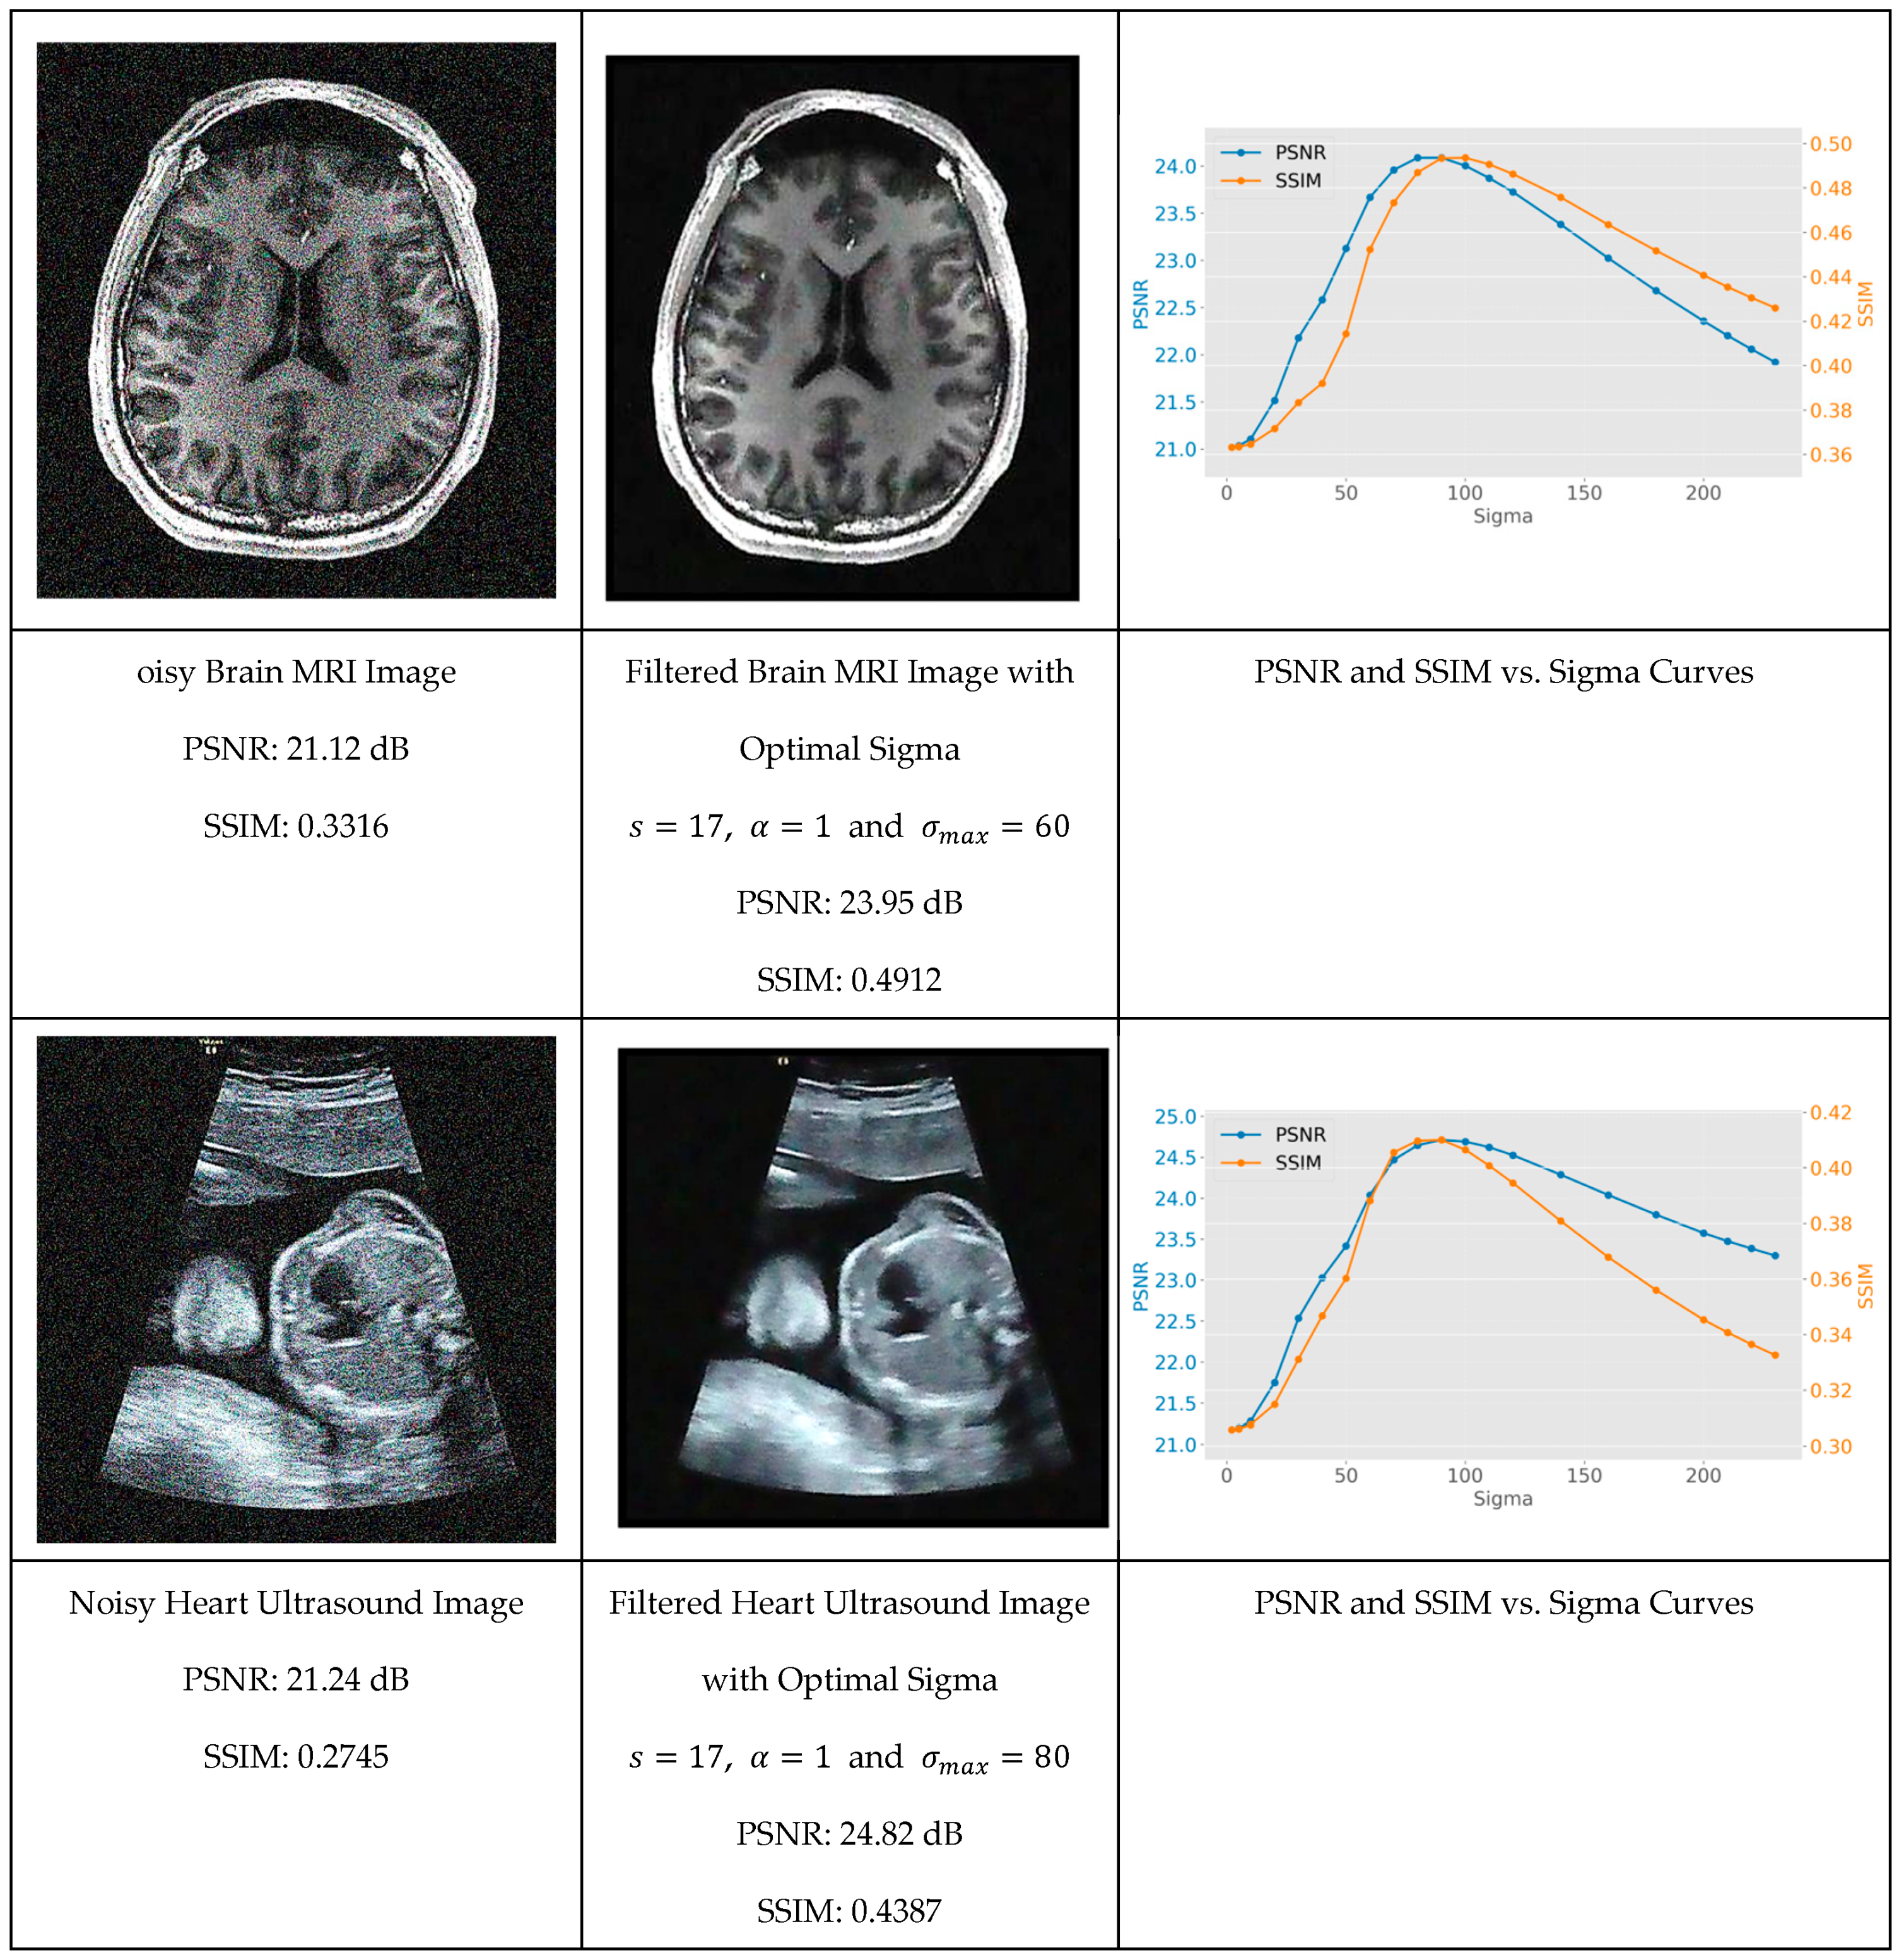

Figure 8 shows the original image with Gaussian noise, the filtered version for σ m a x corresponding to the maximum of the PSNR, and finally the evolution of the PSNR and SSIM as a function of σ . One can see, for each image, the PSNR and SSIM evolve as a function of σ monotonically toward a maximum and then reduce due to over blurring. The σ m a x value corresponds to the maximum PSNR and is called the natural scale of the image.

The experimental results reveal that while the natural scale parameter varied across different images (with test cases showing a range from σ = 60 to σ = 90), it can be systematically identified through careful analysis of PSNR and SSIM metrics. This discovery provides researchers with a methodical framework for parameter optimization that eliminates the traditional trial-and-error approach commonly required in advanced filtering techniques.